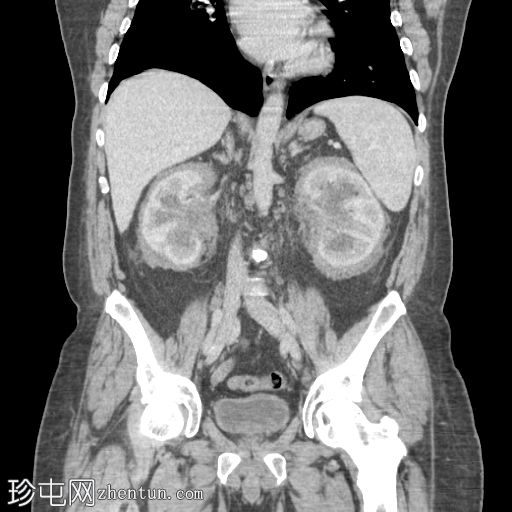

轴位增强扫描(门静脉期)

肾周可见重度、相对均匀的浸润,呈“毛肾征”。肾积水,但无输尿管积水。

肝、脾、胰腺和肾上腺正常。胆囊正常,无胆管扩张。

小肠和大肠(包括阑尾)未进行肠道准备,均正常。

未见其他异常。